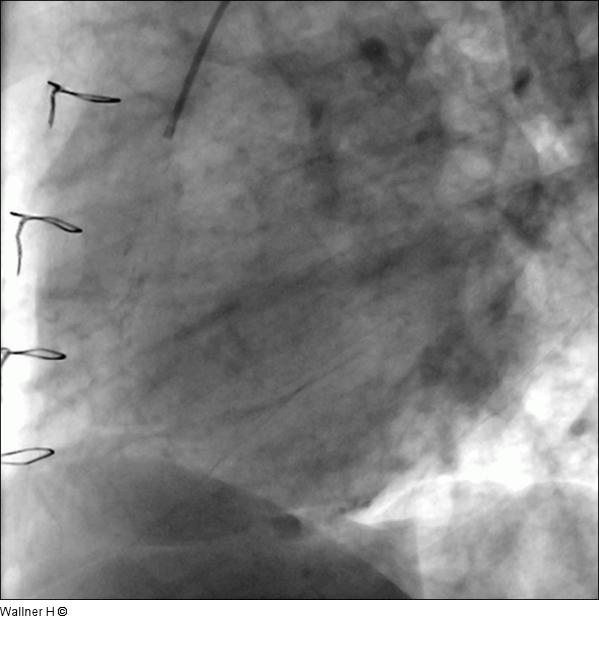

Abbildung 6: Saphena Vena Graft auf die rechte Kranzarterie (RAO 60°/0°) Darstellung mit einem 6F multipurpose Katheter und nach Sondierung mit einem 0,014„ Skipper wire (Invatec™), Einbringung eines Export Katheters (Medtronic™) mit konsekutiver Aspiration von Thrombus. |

Abbildung 6: Saphena Vena Graft auf die rechte Kranzarterie (RAO 60°/0°)

Darstellung mit einem 6F multipurpose Katheter und nach Sondierung mit einem 0,014„ Skipper wire (Invatec™), Einbringung eines Export Katheters (Medtronic™) mit konsekutiver Aspiration von Thrombus. |